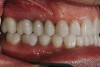

Figure 37  Retracted postoperative view of the IPS e.max restorations.

Figure 37

Figure 38  Retracted right postoperative view of the IPS e.max restorations.

Figure 38